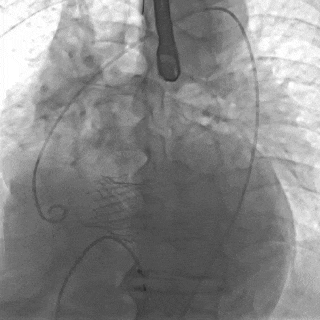

主动脉造影,未见升主动脉瘤影响

术后食道超声

术后食道超声证实主动脉瓣位置及功能正常,未见明显反流及瓣周漏。